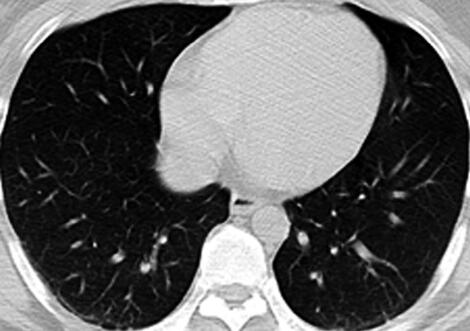

5.胸部CT:两下肺背段少许模糊斑片影(图1)。

图1